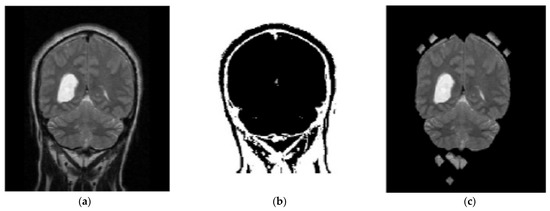

In the proposed segmentation approach, enhanced fuzzy c-means clustering is applied for brain tumor segmentation. In this method, an image’s N pixels are divided into fuzzy c clusters, where c is a positive number and n is a smaller number. Figure 4 and Figure 5 depict various sets of MRI brain images, such as the normal or original image, the binary level image, and the post-morphological operation outcome [37]. The segmentation process is taken as an enhanced version of the fuzzy c-means clustering (EFCMC) algorithm. This includes various stages, as shown in Figure 4 and Figure 5. After performing EFCMC, a final segmented tumor appeared. The proposed segmentation process took less time and was computationally less difficult than other methods.

Figure 5.

Brain images: (a) enhanced; (b) fuzzy c-means 1; (c) fuzzy c-means 2.

A total of 620 MRI scans of the brain were analyzed, 612 of which were deemed normal and 8 of which showed signs of tumor growth (abnormal). It took a few stages of the enhanced fuzzy c-means clustering method to get the area of the brain where the tumor was located. The upgraded fuzzy c-means clustering technique was assumed to be used in the segmentation process. There were several steps involved, as seen in Figure 4, Figure 5 and Figure 6. The tumor was successfully segmented after the EFCMC. The proposed segmentation method was faster and required fewer computer resources than other methods. Figure 6 illustrates the brain MRI images, such as the third stage of the enhanced fuzzy c-means cluster impact and it provides the outcome of the segmented tumor region.

Figure 6.

(a) Fuzzy c-means 3; (b) segmented tumor region.